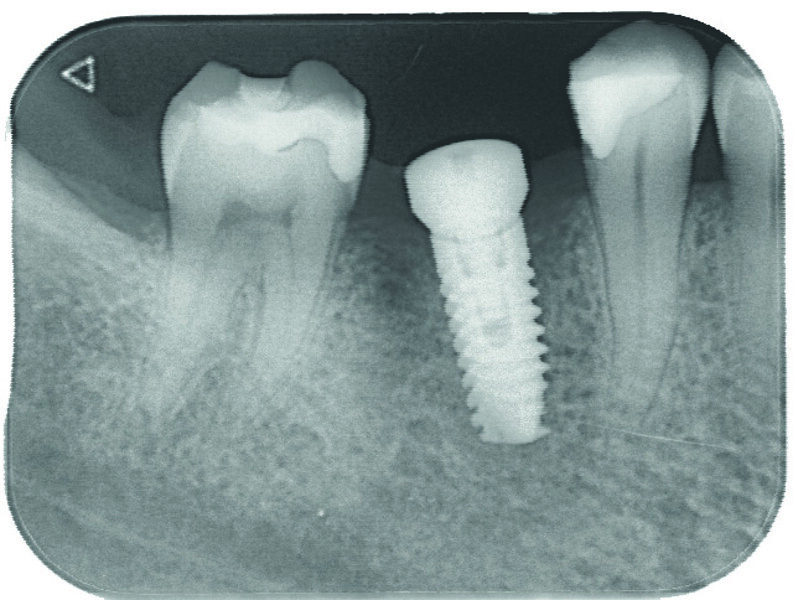

Examen clinique et radiologique L’examen clinique et radiographique met en évidence la possibilité de poser un implant (Figs. 1 et 2).

Fig. 1 : Radio panoramique, on visualise bien le secteur édenté en 46.